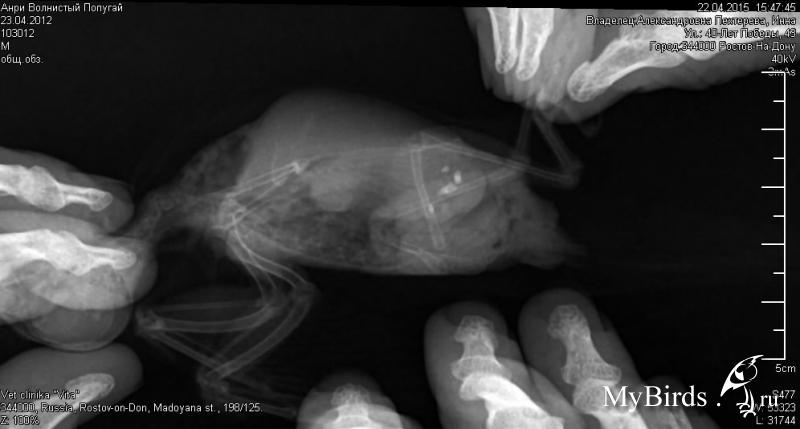

Charlemagne Опубликовано 23 апреля, 2015 Автор #20 Опубликовано 23 апреля, 2015 Добрый день!Вчера сделали рентген. Прикрепляю фото Сказали, что камни, но не смогли определить, где. Должны отправить какому-то светиле-рентгенологу, а на следующей неделе я позвоню - узнаю результат. Но, вообщем, видно, что проблема как раз слева, где и находится проблемная лапка, на которую он не переносит полностью вес тела.Что скажут Ваши специалисты? Четвертый день, как вернула мильгамму - стало получше. Сейчас даю мильгамму, мовалис и траумель (так как мне говорили, что его можно дольше давать, чем травматин, а травматин после 10-12 дней разжижает помет, а у нас итак с этим бывают проблемы).

Zosia Опубликовано 25 апреля, 2015 #24 Опубликовано 25 апреля, 2015 Конкременты на фото (а они конечно есть) с успехом могут быть камушками из минеральной добавки- ЕСЛИ ВЫ ЕЁ ДАЕТЕ. Если же вы не даете никаких таких добавок, и птица не могла погрысть стену/утеплитель, то надо подумать... На счет чтения снимков- лучше меня ГОРАЗДО их читает Маша (ЭКВИ), она училась у Волгиной это делать. Пришлите эти снимки на почту мою, а то я не могу увеличить фото нормально. И конечно малочеткие они,да...Если же минеральную подкормку давали- то снимки "ни о чем". zofia68@mail.ru

Charlemagne Опубликовано 30 апреля, 2015 Автор #25 Опубликовано 30 апреля, 2015 Всем добрый день. Фото отправила. Рентгенолог клиники тоже сказал, что камни в желудки и могут быть кусочками минеральной смеси - у него висит сепия. Сказал, что нужно переделать рентген через 3 недели.По его состоянию - я в отчаянии, я вернула мильгамму, даю мовалис, траумель, но ничего не помогает (на 3-й день после возвращения мильгаммы стало лучше - опять сидел, правая лапка нормально работала, а на этой неделе опять лег, хотя ничего не меняла). Не знаю, что делать. Ужасно больно смотреть на все это. Хорошо, хоть, ходит есть.

Charlemagne Опубликовано 7 мая, 2015 Автор #26 Опубликовано 7 мая, 2015 Перед праздниками отправило снимки Зосе по почте. К сожалению, увидели опухоли у него, сказали надежды нет. Давать обезболивающие и противовоспалительные. Противовоспалительные - ибупрофен. Только я не поняла - давать и ибупрофен и какое-то обезболивающее (например, мовалис), или и то, и другое, или чередовать ибупрофен и мовалис (ведь ибупрофен больше 5-6 дней без перерыва давать нельзя)? Сейчас даю детский нурофен по 0,1 мл в день.Еще у нас проблема с намином - мазали мы мазали левомеколью, и вот вчера он отодрал желтую корочку клювом, а там - по-моему кость видна. Вот так это выглядело вчера вечеромК утру он отковырял всю корочку и выглядело это такСейчас обрабатываю 3-4 раза в день хлоргекседином, потом левомеколью. Все жердочки протерла хлоргексидином. Пыталась обвязать жердочки джутовой веревкой, но он в ужасе убежал с жердочек и 3 часа висел на решетки клетки, уцепившись клювом и лапами. Пришлось снять веревку. Подскажите, что делать, чтобы это зажило - может, еще какая ранозаживляющая мазь нужна. Читала, что нужно мазать ретинолом (витамином А), еще попадалась информация, что после мирамистина нужно обрабатывать смесью дицинона (30 мл) и 2 % новакаина (30 мл). Помогите, пожалуйста. Думаю, что он не становится на правую лапу именно из-за намина. Пока опухоли его не очень беспокоят (только проблемы с левой лапкой). Хочется, чтобы то время, которое ему осталось, он прожил без дополнительных проблем, чтобы хоть одна лапка работала. Очень прошу помощи, сама уже плохо сплю и нервничаю.